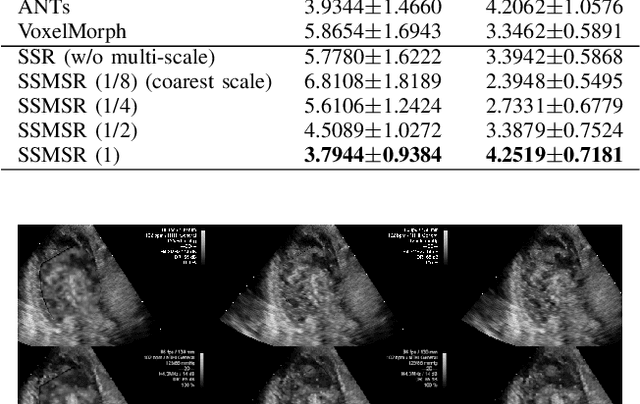

Registration is a fundamental task in medical robotics and is often a crucial step for many downstream tasks such as motion analysis, intra-operative tracking and image segmentation. Popular registration methods such as ANTs and NiftyReg optimize objective functions for each pair of images from scratch, which are time-consuming for 3D and sequential images with complex deformations. Recently, deep learning-based registration approaches such as VoxelMorph have been emerging and achieve competitive performance. In this work, we construct a test-time training for deep deformable image registration to improve the generalization ability of conventional learning-based registration model. We design multi-scale deep networks to consecutively model the residual deformations, which is effective for high variational deformations. Extensive experiments validate the effectiveness of multi-scale deep registration with test-time training based on Dice coefficient for image segmentation and mean square error (MSE), normalized local cross-correlation (NLCC) for tissue dense tracking tasks. Two videos are in https://www.youtube.com/watch?v=NvLrCaqCiAE and https://www.youtube.com/watch?v=pEA6ZmtTNuQ